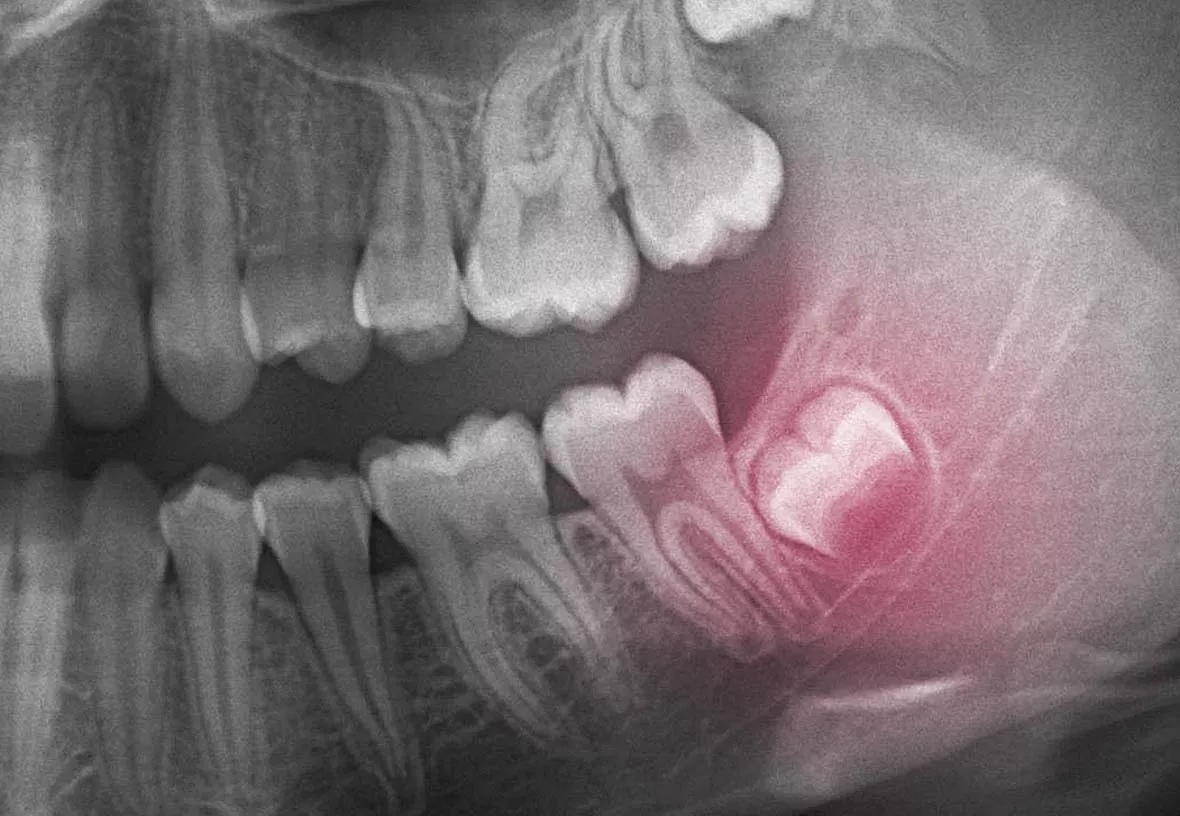

Your wisdom teeth are your last adult teeth. These large molars usually emerge behind your second set of molars at the back of your mouth. However, humans have evolved to have smaller jaws, and there is often not enough room in the jaw for the wisdom teeth to emerge correctly. When this happens, they can be crooked or grow under your other teeth and damage them. Your dentist will monitor the development of your wisdom teeth and recommend their extraction if they aren’t growing correctly.

The wisdom teeth are usually removed before they break through the gums. That means they need to be removed through surgery. Your dentist will make incisions near each tooth and then remove them. The treatment is done with a local anesthetic (freezing), and your dentist may also give you a mild sedative to help you stay relaxed during the procedure. After your wisdom teeth are removed, your dentist will close the incisions with sutures. You will need to return to your dentist’s office in about a week to have the sutures removed.